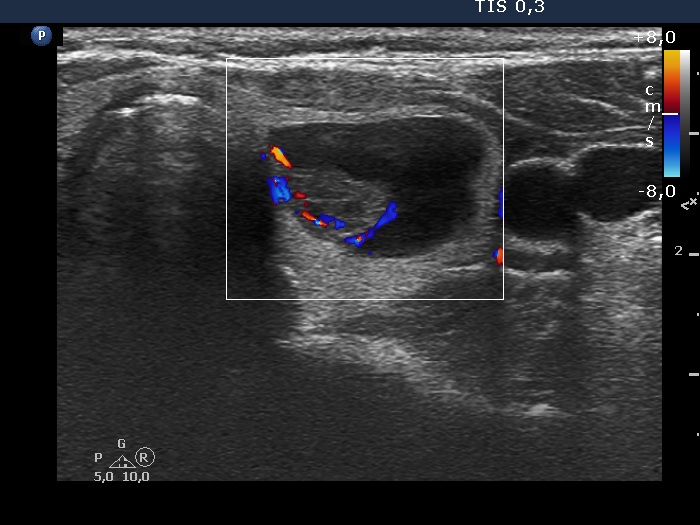

First session of sclerotherapy (ultrasonographic picture 3)

Left lobe, another transverse scan. This is an echonormal part of the mass.